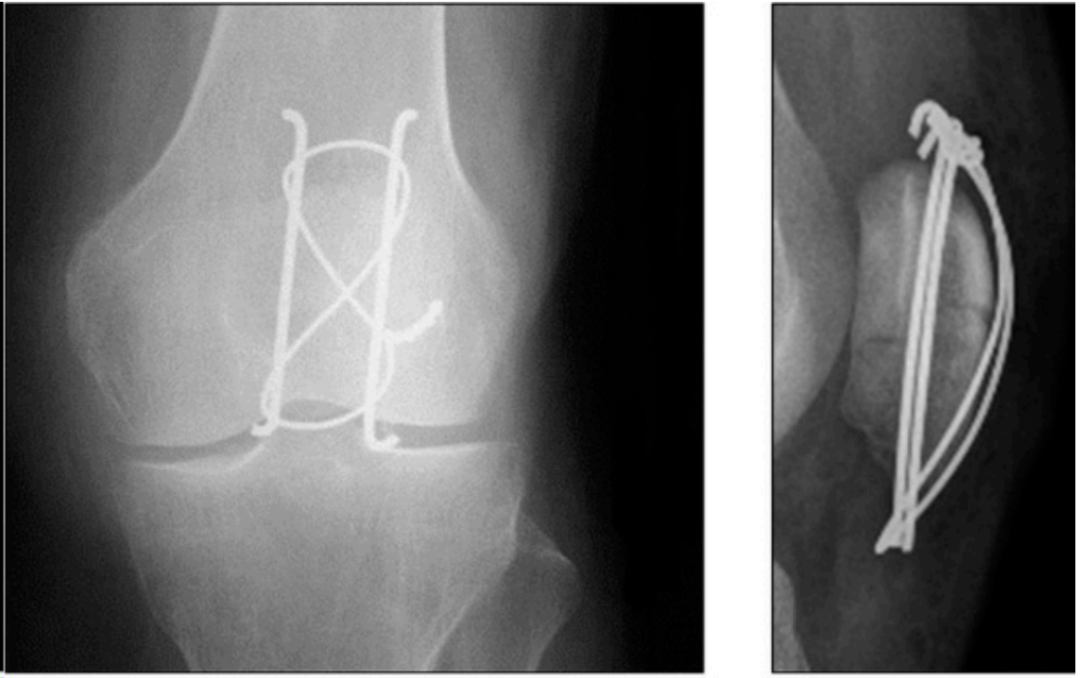

空心螺钉固定(见图2)的引入是为了减少克氏针引起的软组织刺激。该理论认为,与光滑钢丝相比,螺钉还能提供更大的刚度和更强的抗拉伸负荷能力。然而,螺钉头部的存在已被证明会降低结构在循环加载测试中抵抗间隙形成的能力。在该技术中,植入两根平行的空心拉力螺钉,以90度角穿过骨折部位。然后外科医生可以选择通过螺钉以8字形配置添加钢丝。

该技术在生物力学研究中显示出优于单独TBW的稳定性、更低的并发症率和更好的功能结果。

图2. 展示了使用空心螺钉加额外钢丝治疗横行髌骨骨折。

双螺距埋入式加压螺钉加额外缝线张力带已表现出优于标准带头的螺钉固定的生物力学性能,显示出结构刚度增加、骨折块间活动减小、抗失效能力增强以及固定强度更大 。Martin等人证明,无头螺钉结构的平均临床失效强度几乎是带头螺钉结构的两倍。Alayan等人发现两种固定类型的结果相当,但与钢丝和空心螺钉结构相比,埋入式加压螺钉和缝线固定显示出更大的骨折间隙。在一项回顾性研究中,Busel等人评估了使用带头的空心螺钉和高强度不可吸收缝线进行固定,在50例患者的系列中显示了高达96%的愈合率和低至8%的有症状内植物发生率。他们研究中四例有症状内植物中的三例是由于螺钉突出所致。螺钉固定的并发症情况与TBW相似,但金属内植物突出较少。然而,鉴于螺钉比钢丝直径更大,因此有更高的风险穿破髌骨关节面并导致骨折延伸或粉碎。